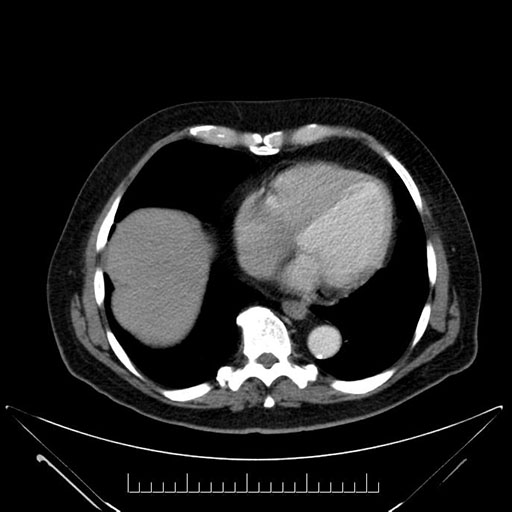

Whipple (pancreaticoduodenectomy) [case 7]

Axial - stented